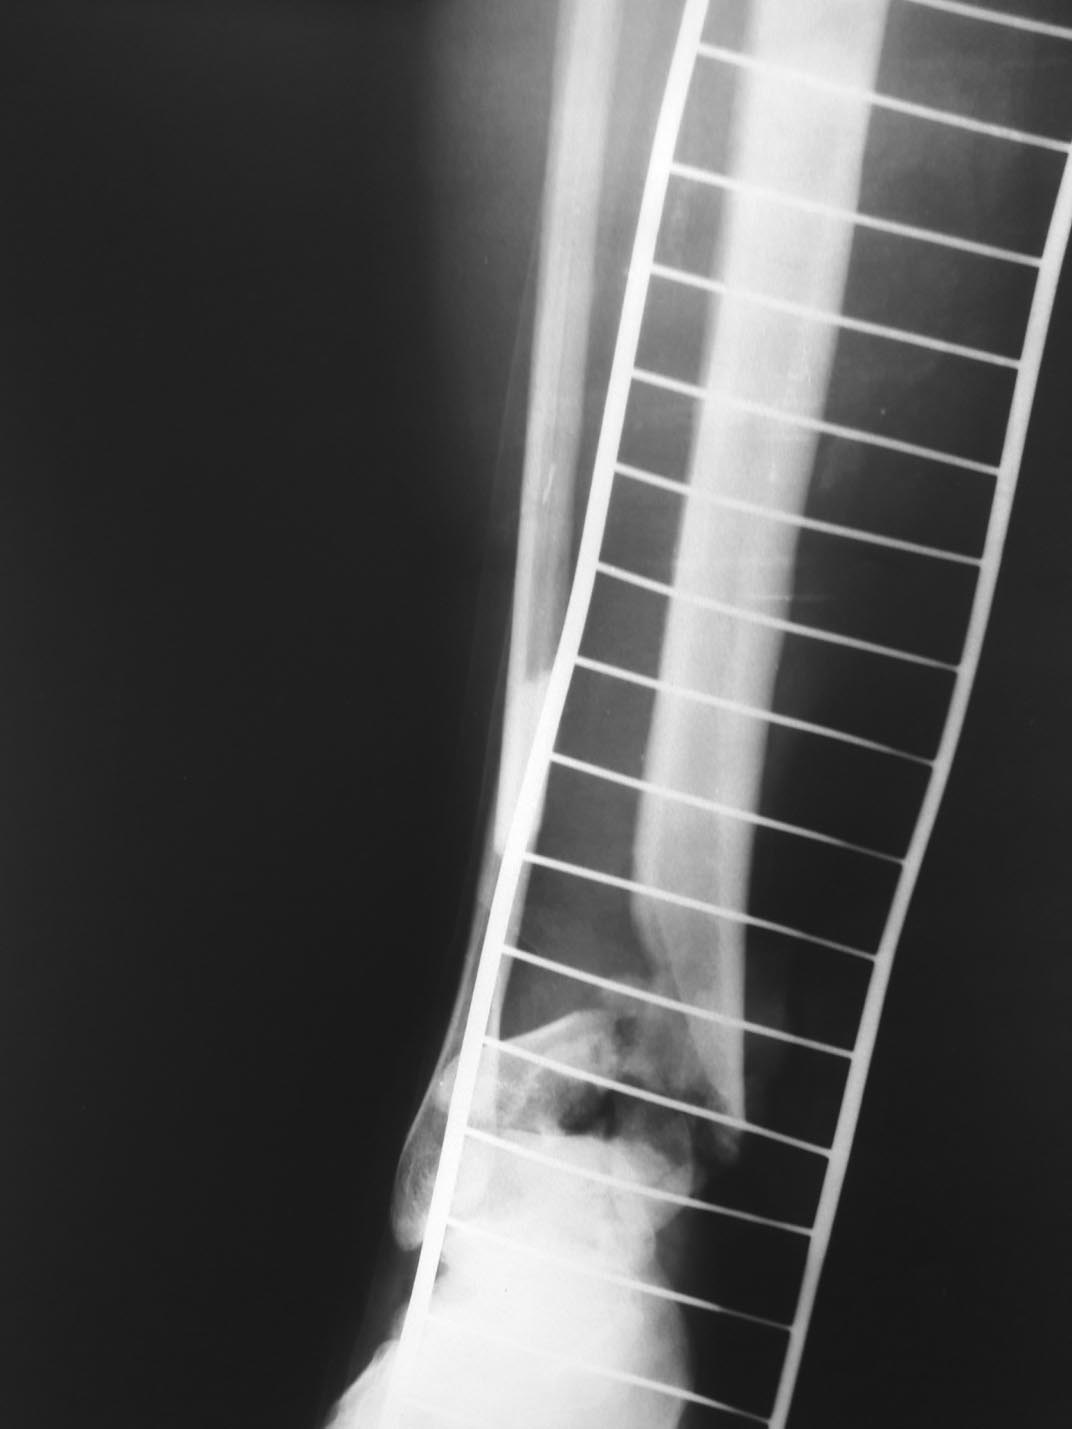

В приемном отделении пациентка осмотрена дежурным травматологом, реаниматологом. На основании клинических и рентгенологических данных поставлен диагноз: Открытый оскольчатый в\суставной перелом дистального метафиза б\берцовой кости, н\3 м\берцовой кости правой голени со смещением отломков(тип IIIА по Gustillo-Anderson, Каплана –Марковой IIIБ) .

В экстренном порядке выполнен временный остеосинтез правой голени и стопы АНФ, ПХО открытого перелома правой голени. Интраоперационно при ревизии отмечается обширный дефект суставной поверхности и дистального отдела б\берцовой кости правой голени.

26.11.16 воспаление, гнойное отделяемое по спице над переломом. Выполнялись перевязки, антибиотикотерапия. В аппарате выполнено сближение проксимального и дистального отломков.

На данный момент при осмотре отмечается умеренный отек н\3 голени и стопы в области раны спокойно, швы сняты частично. В области спиц спокойно. АНФ стабилен. Ишемических и неврологических расстройств правой нижней конечности нет.

Предположительная тактика: перемонтаж АНФ, проксимальная остеотомия б/берцовой кости, формирование дистракционного регенерата на длину смещенной м/берцовой кости.